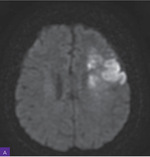

Rycina 2A, B. Rezonans magnetyczny głowy. Widoczne rozsiane ogniska i nieco większe obszary niedokrwienne w fazie ostrej z zakresu unaczynienia gałęzi tętnicy lewej środkowej mózgu, a także rozsiane zmiany wcześniej przebytych ognisk niedokrwiennych z zakresu unaczynienia tętnicy prawej środkowej mózgu

Diagnostykę poszerzono o badanie rezonansu magnetycznego (MR) w protokole udarowym. W badaniu opisano rozsiane ogniska i nieco większe obszary niedokrwienne w fazie ostrej z zakresu unaczynienia gałęzi tętnicy lewej środkowej mózgu, a także rozsiane zmiany wcześniej przebytych ognisk niedokrwiennych z zakresu unaczynienia prawej tętnicy środkowej mózgu (ryc. 2).